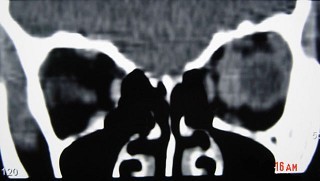

女性,38岁,右侧眼球运动障碍伴眼球突出4个多月,CT扫描如图,请选择正确的描述和答案()

-